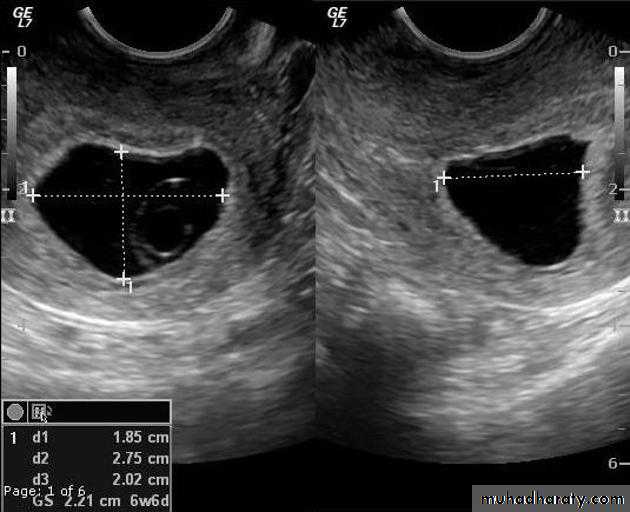

Blighted ovum

Anembryonic pregnancy is a form of a failed early pregnancy, where a gestational sac develops, but the embryo does not form. The term blighted ovum is synonymous with this, but is falling out of favour and is best avoided.

Radiographic features

Ultrasound

An anembryonic pregnancy may be diagnosed when there is no fetal pole identified on endovaginal scanning , and:

the size of the gestational sac is such that a fetal pole should be seen: MSD ≥25 mm on TVS (by RCOG criteria)